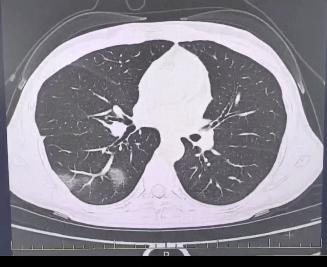

程女士病情紧急,随即被送往医院接受治疗。杭州市第三医院呼吸科专家团队迅速为她制定了专属的治疗计划,医护人员全天候精心护理。经过连续7天的不懈努力,程女士最终痊愈,并顺利出院。

连续坚持三天后病情加剧,她在会议上频繁咳嗽,呼吸急促,体温攀升至39.7℃。同事紧急将她送回医院,发现她的多片肺叶呈现“白肺”症状,多项生理指标异常,最终被确诊为重症流感。

病毒性肺炎可由流感病毒引起,亦可能继发于细菌感染。此病症常伴有高烧、干咳等典型症状,病情严重时可能导致呼吸功能衰竭。程女士所患的“白肺”即为流感病毒导致的肺部感染严重病例。